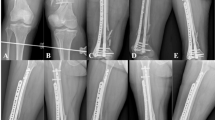

(a) Placement of rim plate and engagement of wires. (b) Reduction of proximal and distal fragments using reduction clamp. (c) An additional anterior cortical plate fixation for anterior cortical split fragment. (d) Tightening of vertical wires. (e) Postoperative radiographs show the rim-plate-augmented separate vertical wiring with supplementary fixation using two anterior cortical plates and embedded screws. All identified fragments were anatomically stabilized. (f) After 6 months, radiologic bony union was achieved and range of motion was fully recovered without extension lag.